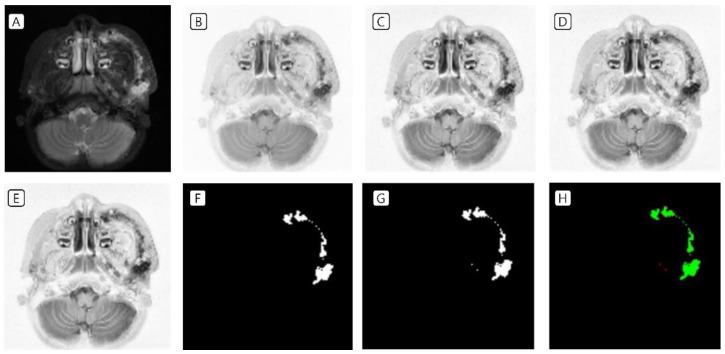

Deep Learning for the Automatic Segmentation of Extracranial Venous Malformations of the Head and Neck from MR Images Using 3D U-Net.

T2-weighted MRI from 53 patients with extracranial VMs in the head and neck region was used for annotations. Preprocessing management was performed before training. Three-dimensional U-Net was used as a segmentation model. Dice similarity coefficients were evaluated along with other indicators.

Dice similarity coefficients in 3D U-Net were found to be 99.75% in the training set and 60.62% in the test set. The models showed overfitting, which can be resolved with a larger number of objects, i.e., MRI VM images.